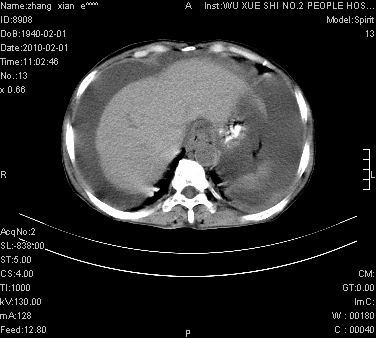

标题: CT24434:70岁 女 腹胀,腹水原因待查 [打印本页]

标题: CT24434:70岁 女 腹胀,腹水原因待查

大量腹水,脾脏囊性占位,子宫颈占位,右侧腹股沟淋巴结肿大,建议+c,先查妇科。

大量腹水,脾囊肿可能性大,建议增强

大量腹水,右肾、脾囊肿可能性大          考虑左侧附件区占位,建议增强